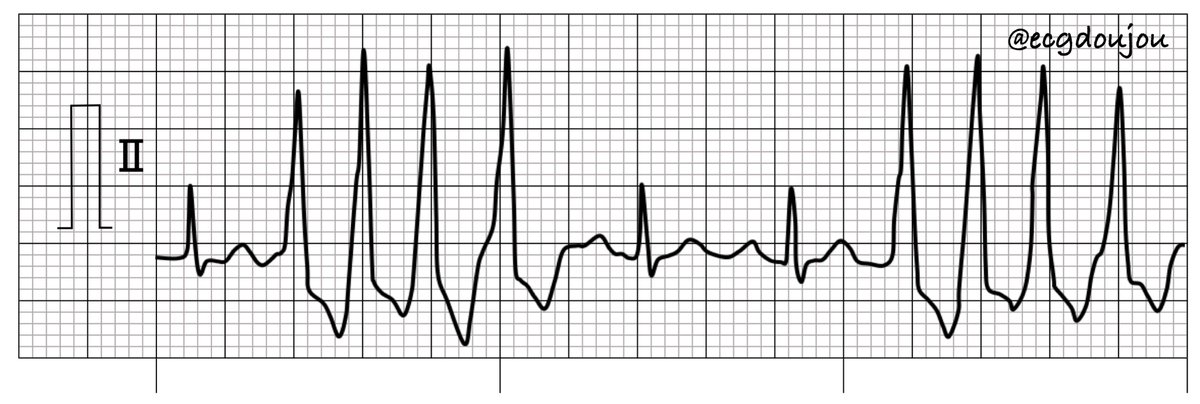

正解はウェンケバッハ型Ⅱ度房室ブロックでした❗️ 心電図道場公式LINE https://t.co/sm1GOXIBdL 解説動画 https://t.co/yz0pnGfpz8

こんばんは👍心電図道場です‼️ 今日も1問心電図です💪 リズムを読んで答えてください🎵